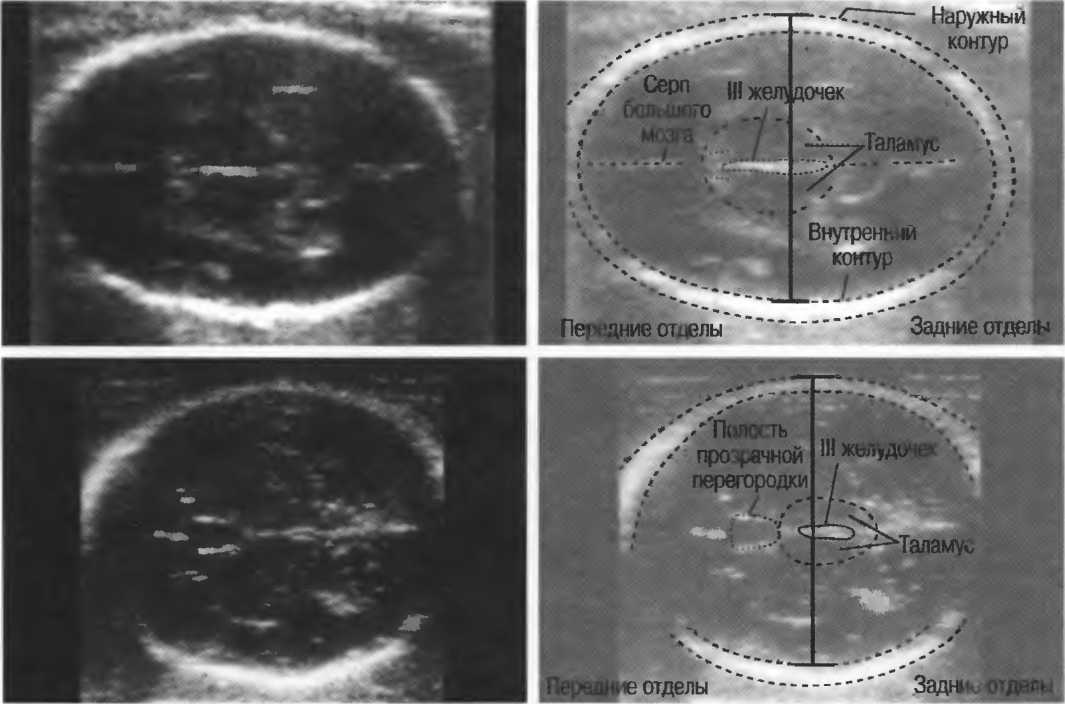

- При удовлетворительном качестве изображения можно получить изображение полости прозрачной перегородки головного мозга у 35-недельного плода (рис. 23). Этот тест можно использовать для контроля качества в случаях, когда нет фантома. Данный тест необходимо проводить каждые 3 мес.

Рис.23а. На любом приборе должна визуализироваться полость прозрачной перегородки головного мозга 35-недельного плода.

Рис.23б. На аппарате высокого класса полость может визуализироваться в более ранние сроки беременности.